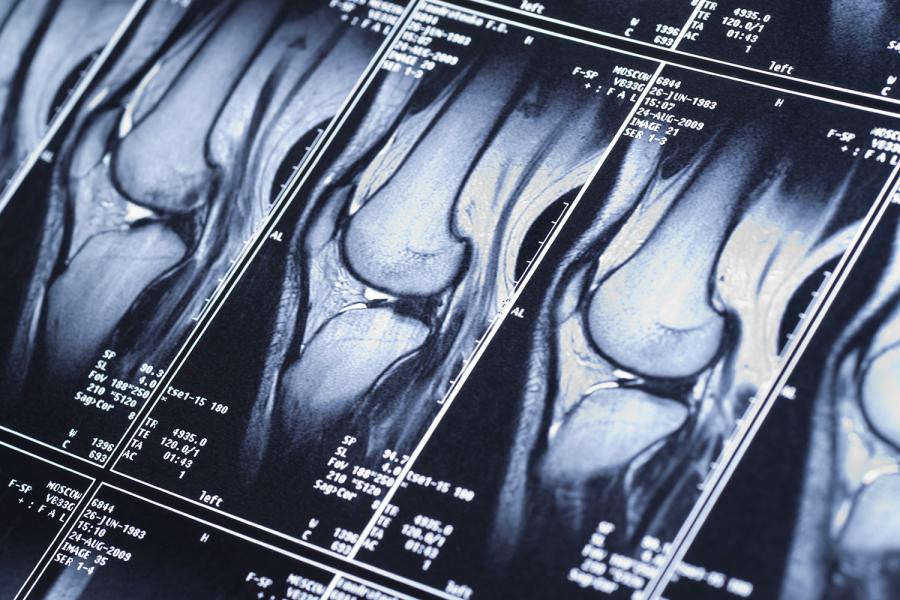

Deep Learning–Based Imaging Biomarkers for Knee Osteoarthritis

We are developing an automated tool to detect knee osteoarthritis and predict the likelihood of knee replacement over the course of a decade. The tool, which we plan to make available on the internet, will be based on neural networks trained on radiographs, MRI, and clinical data. When presented with images of the whole knee joint, the system will quickly evaluate disease presence and the likelihood of progression.

This research, supported by the National Institute of Arthritis and Musculoskeletal and Skin Diseases under award number R01AR074453, has the potential to improve our understanding of osteoarthritis, inform therapy, and lead to more effective clinical trials.